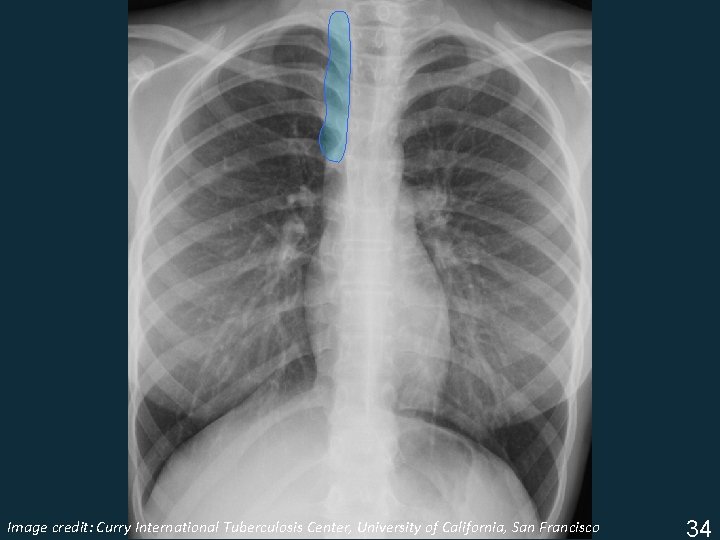

Lymphadenopathy (LAN) § Non-specific terms: • Mediastinal widening • Hilar prominence § Specific patterns: • Particular station enlargement (location) Important to know what “normal” should look like in order to recognize “abnormal” ISTC TB Training Modules 2009 33

Image Tuberculosis Center, University of California, San Francisco ISTC TBcredit: Training Curry Modules. International 2009 34

Lymphadenopathy § Infrahilar window (right hilar and/or subcarinal) § Left hilar § Subcarinal Image Tuberculosis Center, University of California, San Francisco ISTC TBcredit: Training Curry Modules. International 2009 35